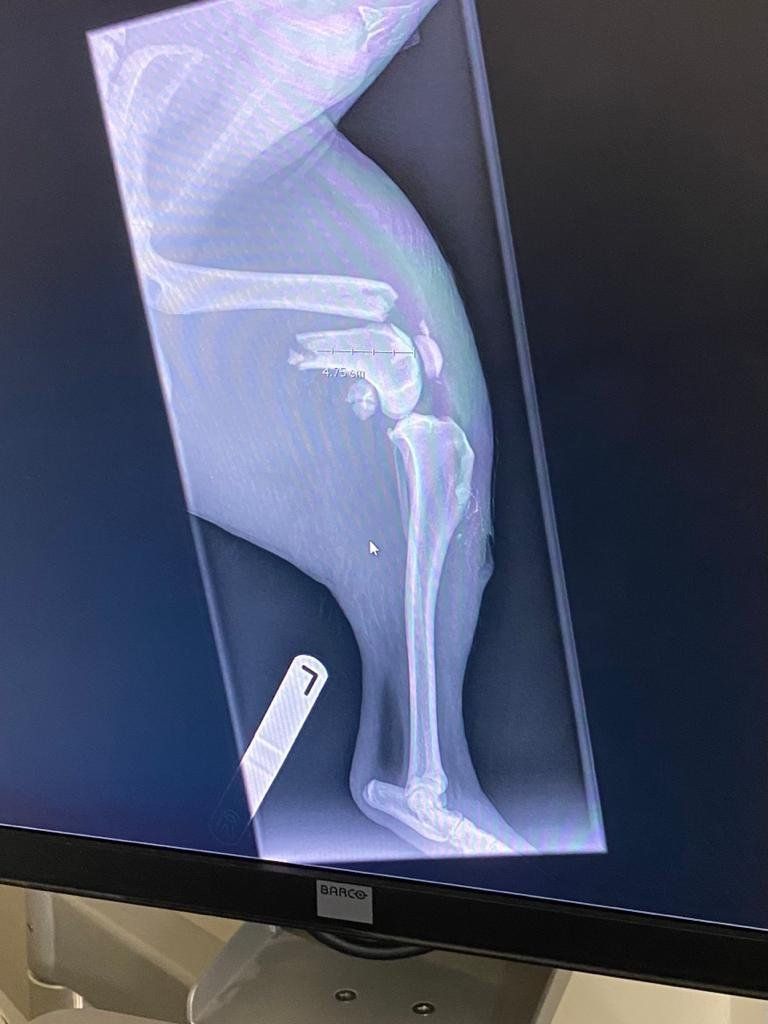

주인에 품으로 돌아간 개는 바로 치료를

받기 위해 병원으로 갔으며, 검사를 진행

하였습니다. 놀랍게도 횡격막 파열 등의

심각한 부상없이 골절만 있었다고 합니다.

말도 안되는 높이에서 떨어진 후 단순

골절상만 입은 개는 앞으로 써야 할 운을